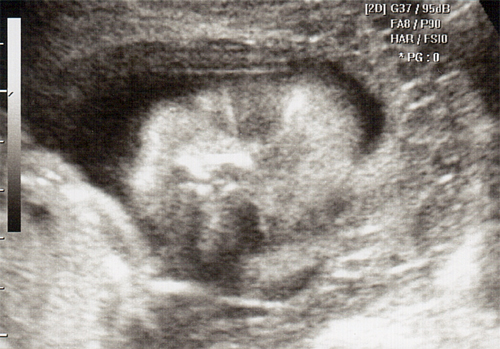

강아 ^^ 21주 강이의 정밀 초음파를 봤어 일반 초음파 보다는 더 정밀하게 나오더라구 엄청 커버린 강이가 한눈에 보이지 않을정도로 이제는 초음파 기계가 작아 보이더라..

강이 얼굴을 딱~ 보는순간.. 심장이 멈추고 코를 보는순가 다시 심장이 뛰기 시작했어 딱.. 아빠 코를 닮았더라 ^^:.. 이쁜자식...